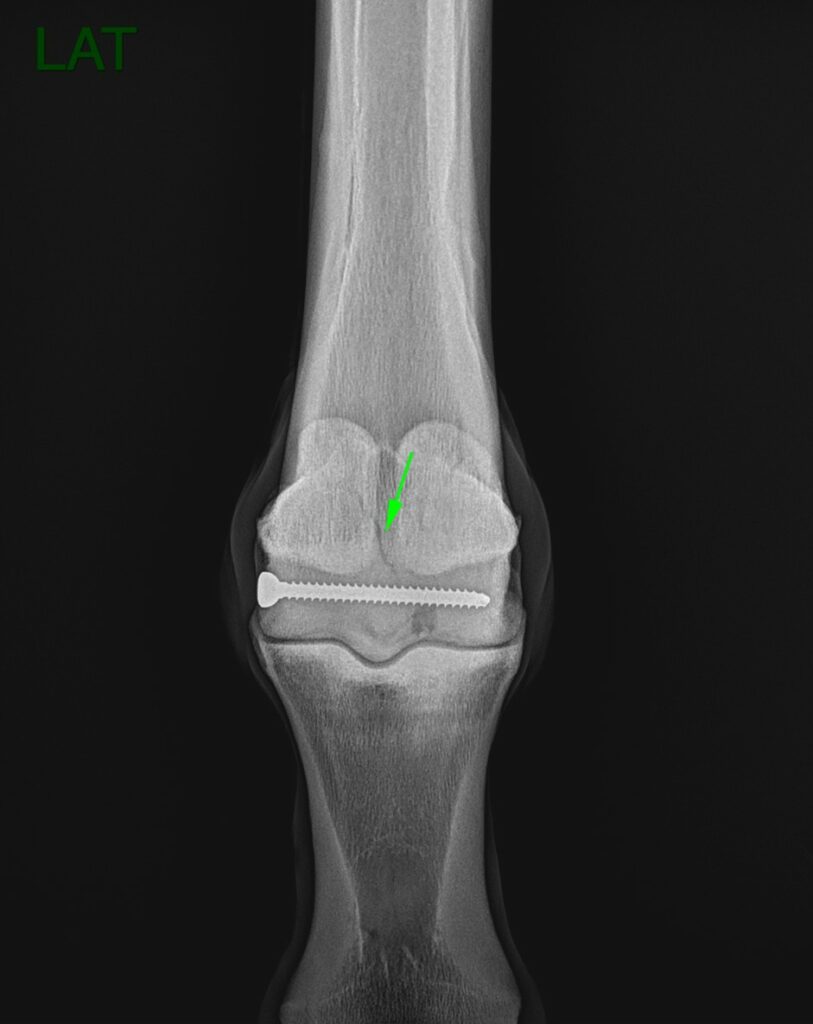

Radiographic findings

The primary concern identified in the radiographs was a faint line at the proximal aspect of the sagittal ridge, potentially indicating a fracture line (Figure 1). Additionally, an area of osteolysis was observed at the medial parasagittal groove of the medial condyle of the third metacarpus. This osteolytic area was most likely in communication with the joint. There was also a surgical implant (screw).